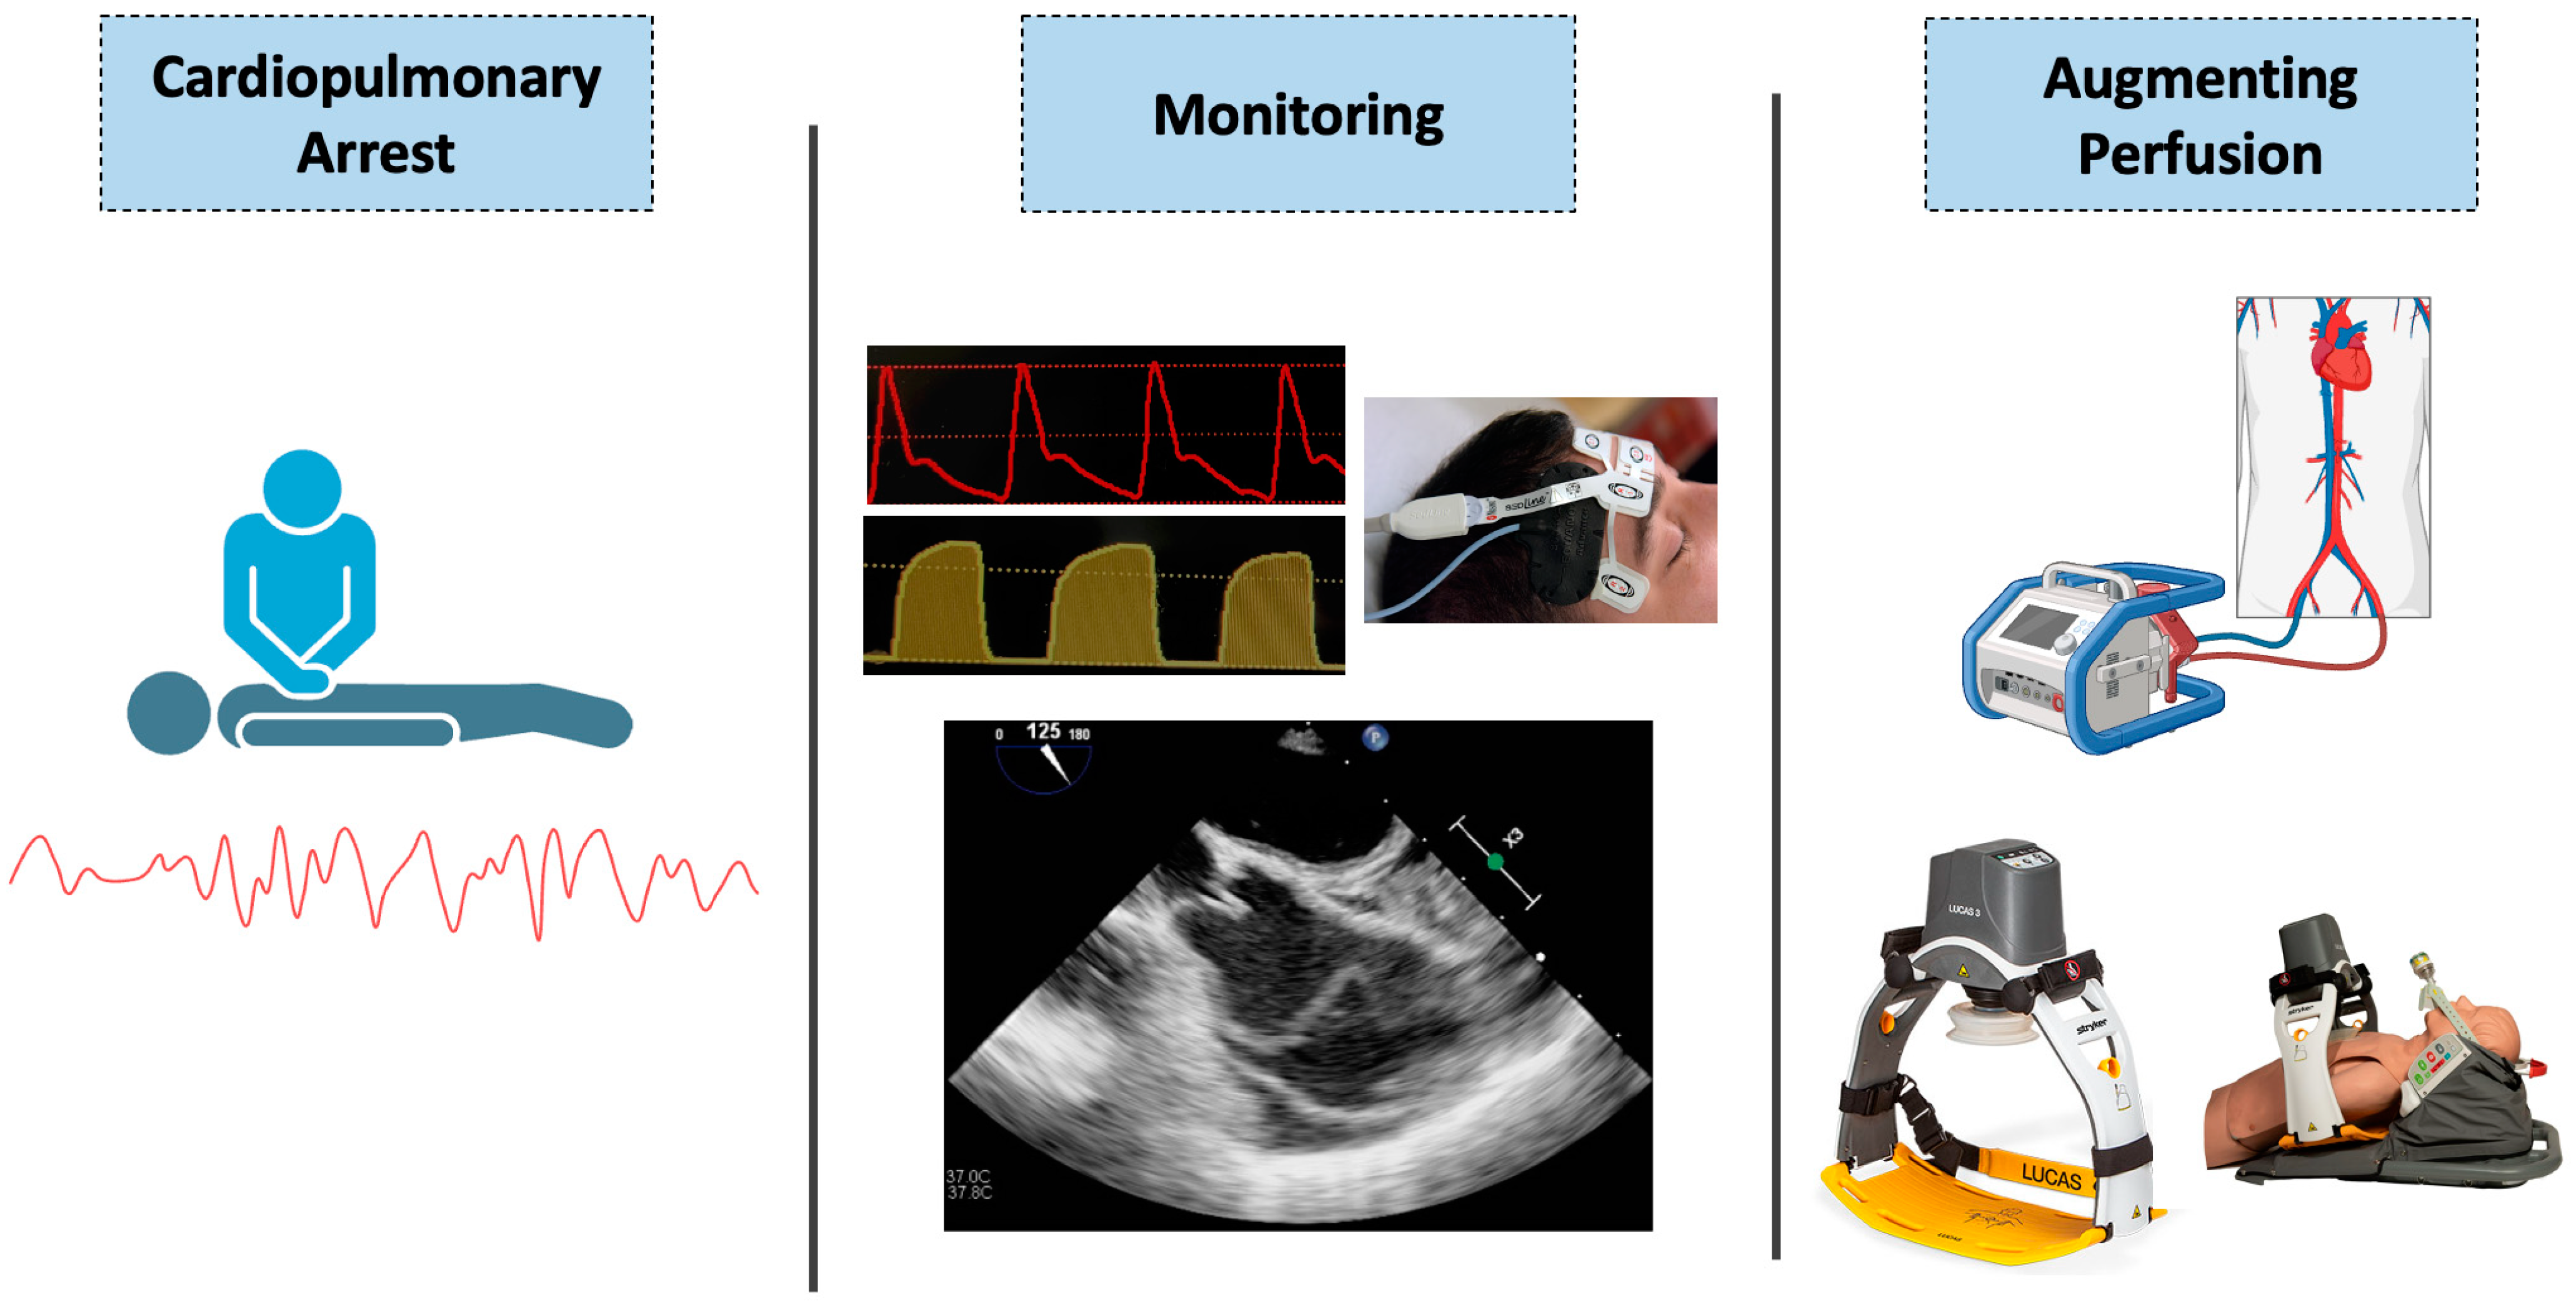

Physiology-Guided Resuscitation: Monitoring and Augmenting Perfusion during Cardiopulmonary Arrest

3. Monitoring Perfusion during Cardiopulmonary Resuscitation—Current Strategies

4.1. Regional Cerebral Oximetry

5. Augmentation of Circulatory Support